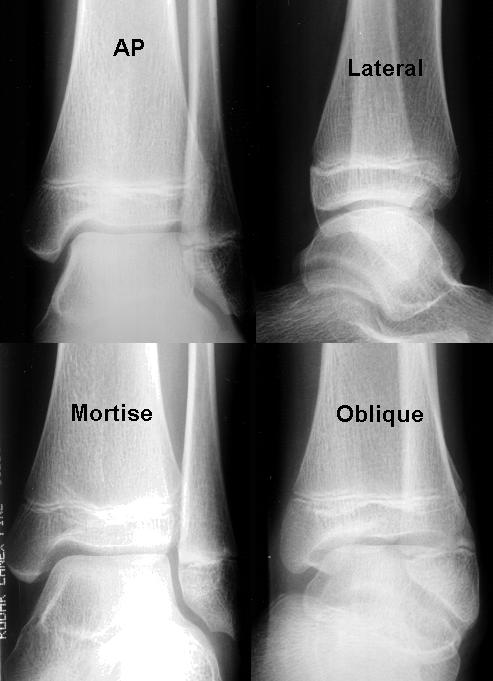

What are all of the potential positions?

Anteroposterior (AP) Projection

AP Mortise – 15-20 Degree Rotation*

AP Medial Oblique – 45 Degree*

AP Lateral Oblique – 45 Degree (optional)

Lateral